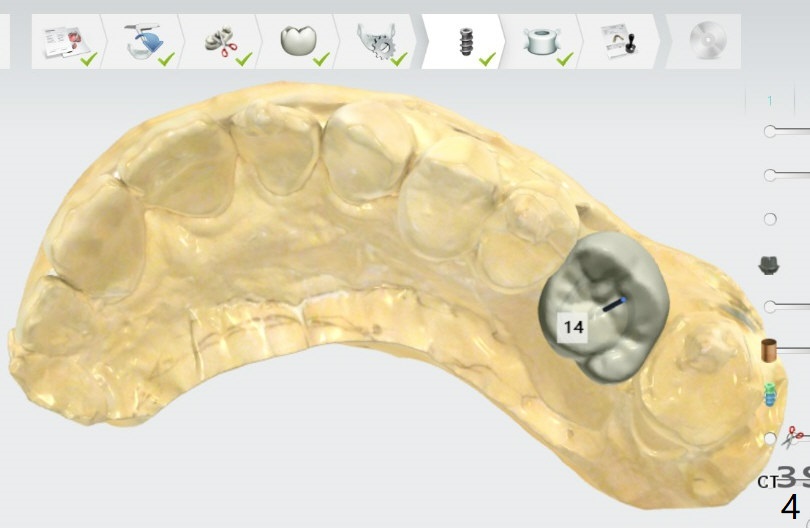

A 49-year-old woman Magicore 5.5x9 or 11(2 or 3).

Return to Upper Molar Immediate Implant Trajectory II  SP 位点保留后